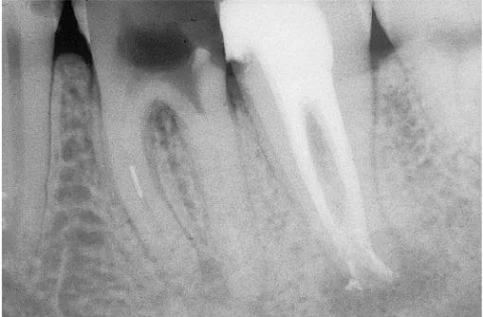

Khi có sự hiện diện của ống gần cong – và vì vậy chân răng chứa ống tủy congnày – sử dụng phương pháp dùng file “chống đoạn cong” là điều bắt buộc khi chuẩn bị ống tủy những chân này. Ống gần của răng cối lớn một dưới cùng với ống gần ngoài của răng cối lớn một trên là 2 vị trí thường xảy ra mài mòn, xuyên thủng nhất (hình 11.118).

Hình 11.118. Bỏ qua việc áp dụng phương pháp “chống đoạn cong” dẫn đến kết quả mài mỏng quá mức thành chân răng và gây xuyên thủng A. Phim trước điều trị. Chú ý độ mỏng của chân gần và độ cong nhẹ của nó. B. Phim sau điều trị: thành xa của chân gần bị mài thủng.